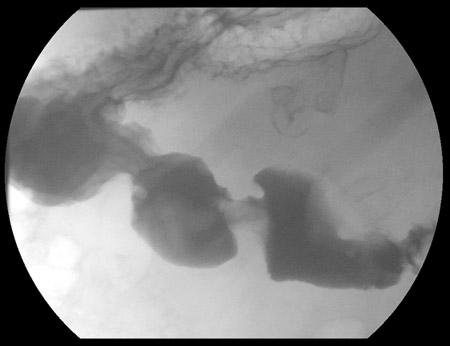

[Figure caption and citation for the preceding image starts]: Gastric submucosal lipoma, upper GI contrast study. Filling defect in the distal antrum and pyloric channel suggesting antral mass prolapsing into pyloric channelFrom the collection of Dr Kimberly Moore Dalal and Dr Steven D. DeMartini; used with permission [Citation ends].